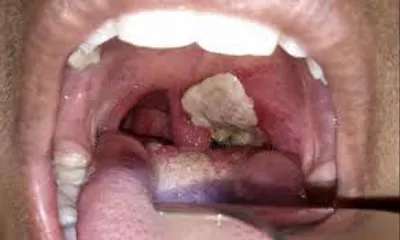

diphtheria

A serious infectious disease which causes inflammation of mucous membranes of the upper respiratory tract caused by Corynebacterium diphtheriae.